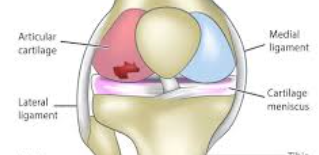

무릎 연골 손상의 주요 증상

인대 손상과의 구별

반월상연골파열과의 구별